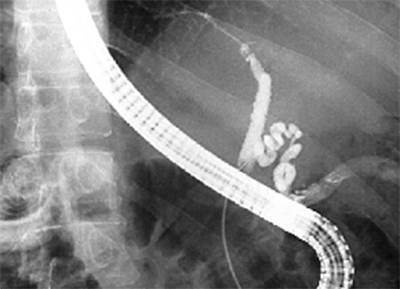

Colangiopancreatografía

Retrógrada Endoscópica